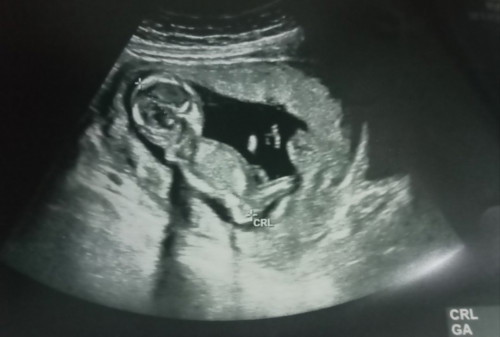

ภาพนี้ตอน13+5ตอนนี้24+1แล้วคะ ผู้ชาย